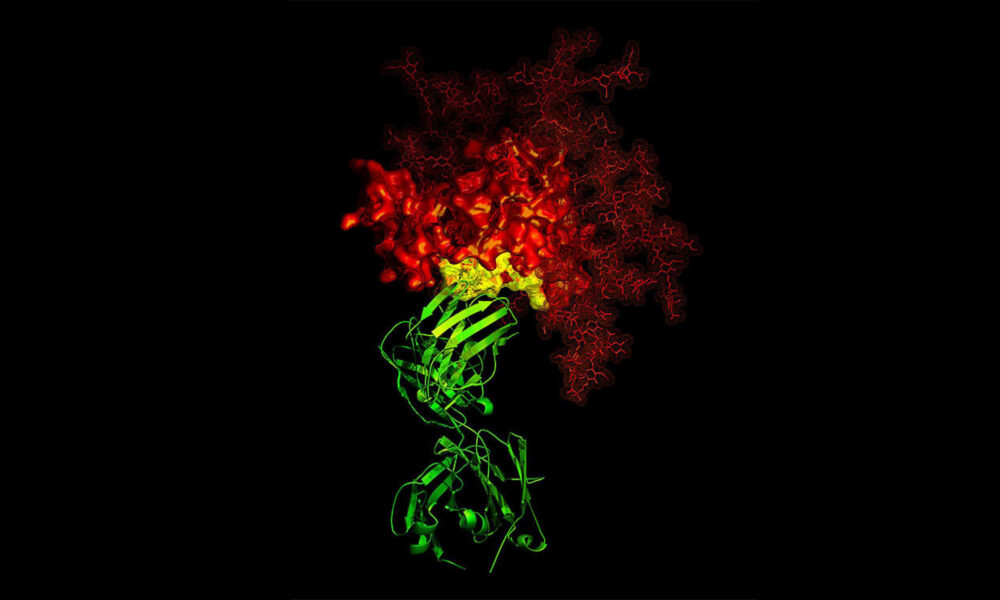

Renovatio 21 traduce questo articolo su gentile concessione del sito di Children of God for Life. Alcuni lo sono e altri no. Un anticorpo...